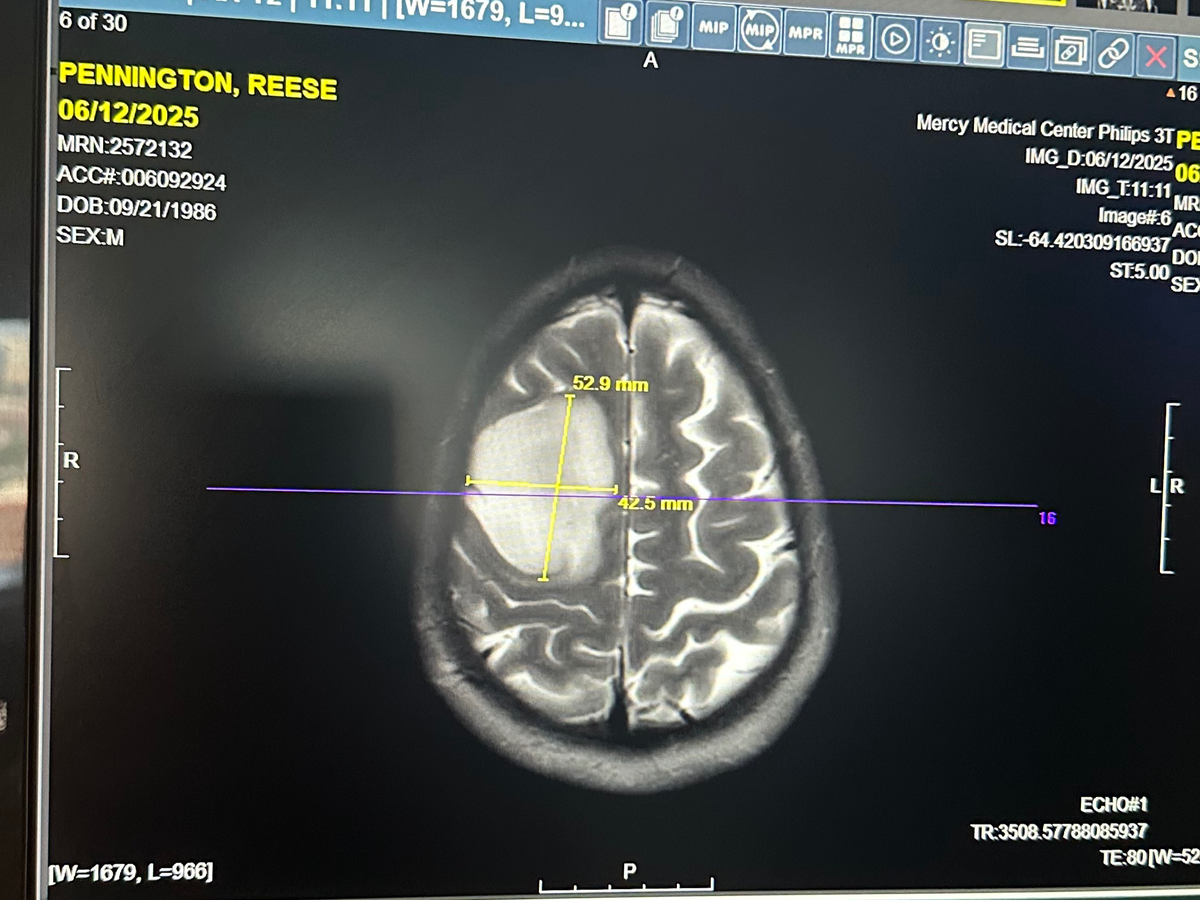

Reese was recently diagnosed with a Grade 2 Oligodendroglioma — a rare, slow-growing but serious primary brain tumor. It’s something no one ever expects to hear, especially at just 38 years old.